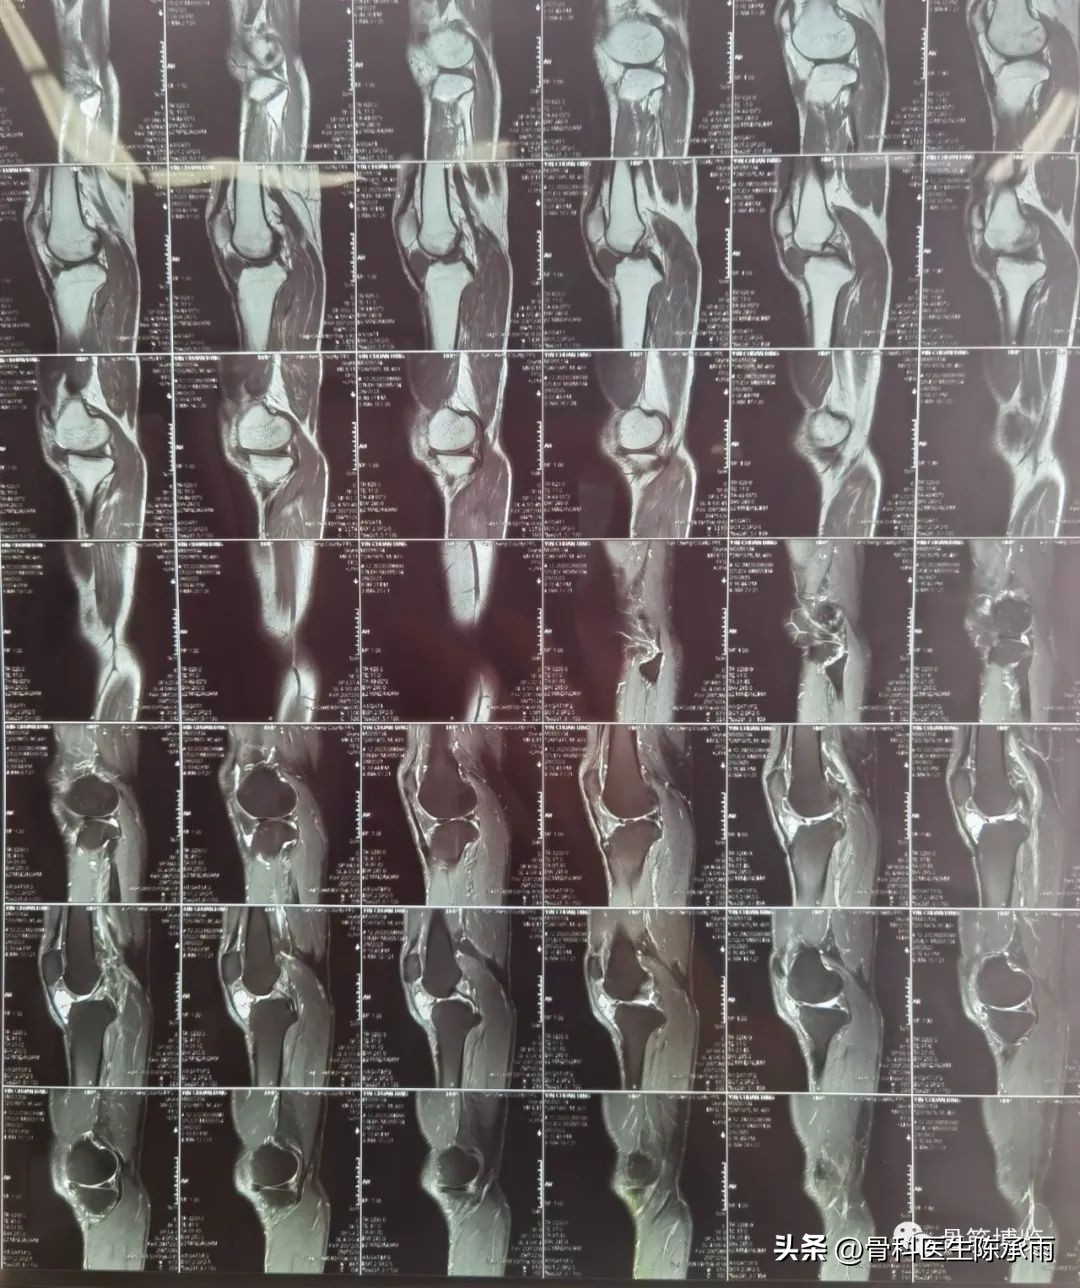

本例为内侧半月板前角巨大囊肿,关节镜下行半月板囊肿引流减压+囊肿前壁及囊壁滑膜切除+半月板缝合术。术中切除全部囊壁内滑膜及前壁及大部分后壁,保留部分后壁组织,以保证半月板前角缝合可靠及稳定。

术前影像